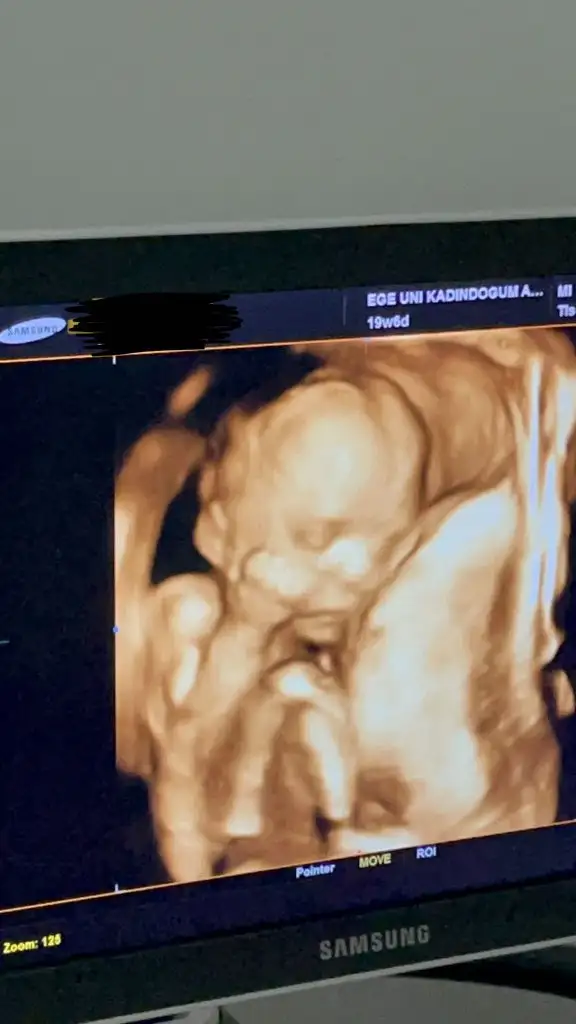

Ah elleriSelam arkadaşlar, ben de az önce doktor kontrolünden çıktım. Kullandığım demir, magnezyum ve d vitaminini yine yazdı. Dün konuşulan bebeğin toplanması, sertleşmesi durumlarını da sordum benim de ara sıra oluyor. Yatar kalkarken hep yan pozisyonda olmaya dikkat et dedi. Günde 15 keze kadar normal dedi, yani saat başında bir olabilir dedi. Ama sürekli oluyorsa problem olur dedi. İlk defa renkli ultrasonda baktı, yüzünü gördümGüzel bir duygu ama ben hala çok yoğun duygular içinde değilim. Bağ kuramadım henüz, anne gibi hissetmiyorum normaldir umarım Bu da oğlumun yüzünü görebildiğim ilk fotoğraf